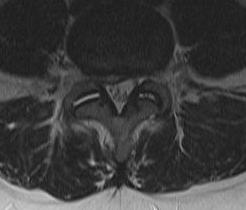

MRI

T2 Sagittal - myelogram

T1 Axial - see nerve root against white fat